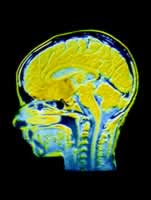

婴儿创伤性脑损伤诊断往往困难,较易误诊。美国匹兹堡儿童医院的一项纳入98例患儿的前瞻性、病例对照研究(Pediatrics 2006,117:325)发现,血液或脑积液中的神经元特异性烯醇化酶(NSE)和髓鞘碱性蛋白(MBP)水平可作为一种筛查婴儿脑损伤的方法。